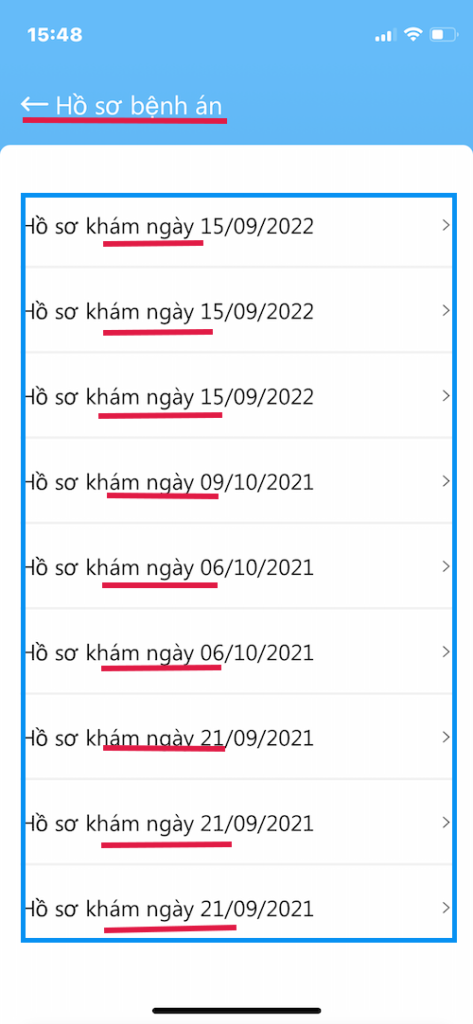

HỒ SƠ BỆNH ÁN

Các phiên khám có lưu hồ sơ

- Hồ sơ kèm ngày đã khám

- Bấm vào hồ sơ sẽ hiện chi tiết tất cả các phiên khám

- Chẩn đoán, toa thuốc, kết quả xét nghiệm…